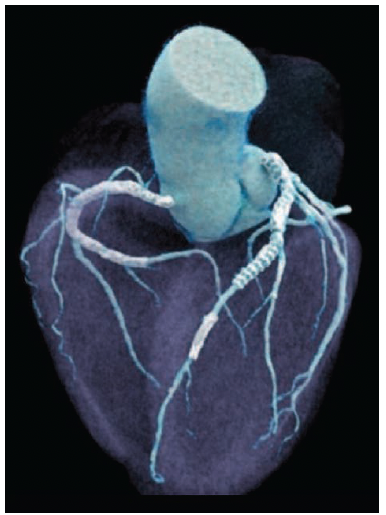

The high level of spatial resolution in a diagnostic cardiac computed tomography angiography (CCTA) scan conducted using photon-counting CT can help clinicians determine whether a patient with cardiac disease also requires an invasive coronary angiography procedure. In this case, a 5’6”, 180 lb male patient with coronary artery disease was scanned on a photon-counting CT scanner (the NAEOTOM Alpha, Siemens Healthineers) for follow-up care after stenting and evaluation for in-stent restenosis. The CT scan, which used a sequential Quantum HD Cardiac CCTA acquisition and was reconstructed in the Best Diastolic phase utilizing a 1024x1024 matrix, was performed at 140 kVp with an estimated patient radiation dose of 4 mSv. The scan revealed not only multiple areas of in-stent restenosis (Figures 1-2), but also soft and hard plaque in non-stented areas (Figures 1-3).

multiple stents.